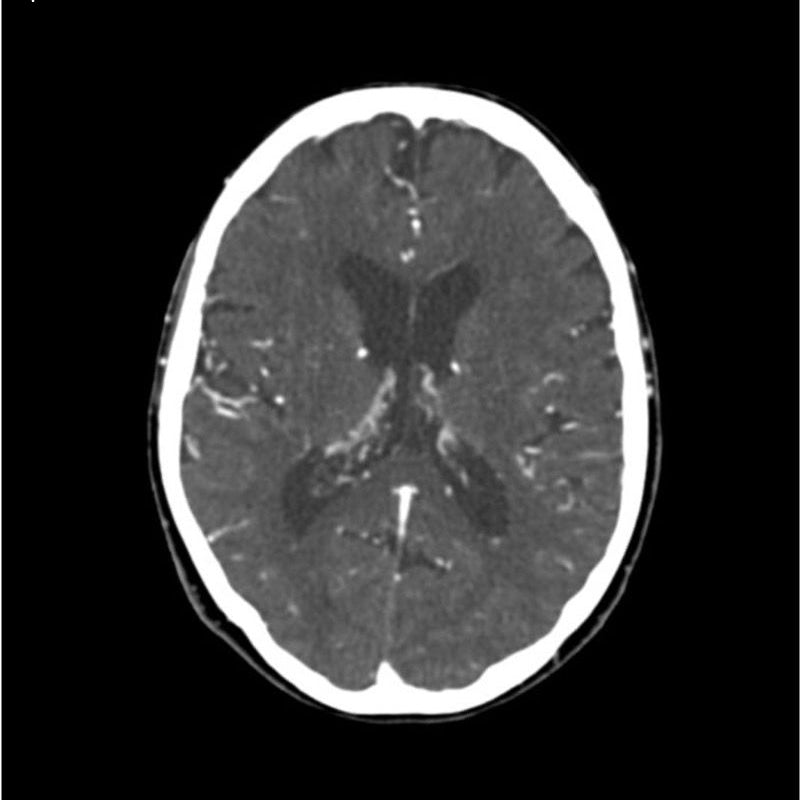

CTA Head and Neck Phantom for CT Scan and X-Ray Training

This phantom simulates a contrast medium enhanced head in arterial phase (CT angiography). The neck and upper thorax are included up to the aortic arch and the fifth thoracic vertebra. The vertex is included until approximately 0.5 cm below skin level. The thoracic phantom section excludes shoulder and back parts that are typically not part of CTA examinations. The interncal carotid artery has calcifications on both sides with moderate stenosis on the right side. Otherwise, the phantom has no significant vascular pathologies.

The phantom can be used in CT (including CBCT) to evaluate and optimize CTA imaging performance and post-processing applications such as vessel segmentation, including AI-enabled applications. It is also nicely suited for training purposes. The phantom provides a detailed and realistic simulation of vascular structures, soft and bone tissue, including small details such as lymph nodes. Air voids are filled with a cellulose-polymer composite of approx. -160 HU.

Realistic simulation of head and neck vessels up to the aortic arch, bone and soft tissues.

Calcifications of the internal carotid artery at the carotid bifurcation on both sides with mild stenosis on the right side.